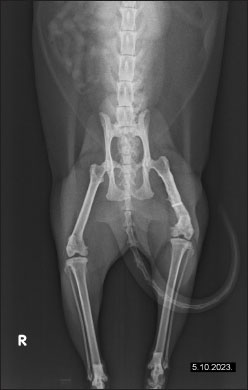

The owner reported continuous improvement, noting that the cat is increasingly bearing weight on the left hind limb, showing fewer signs of pain, and displaying an improved disposition. Follow-up radiographs revealed improvement in the condition of the femur post-therapy (Fig. 4). There is a noticeable improvement in bone structure, indicating enhanced healing and remodeling processes. After 2 months of intensive therapy and visible clinical improvement, the intervals between treatments were further extended. The radiograph shows the bone structure to be more consolidated, indicating effective recovery and remodeling (Fig. 5). Overall, the imaging suggests a positive outcome following treatment. In agreement with the owner, the treatments have continued on a monthly basis, and the cat continues to show progress.

Fig. 4. The radiographs of a cat’s left femur show (a) a ventrodorsal and (b) a mediolateral view demonstrating the femur after 1 month of LT, demonstrating reduced medullary transparency and early signs of bone consolidation.